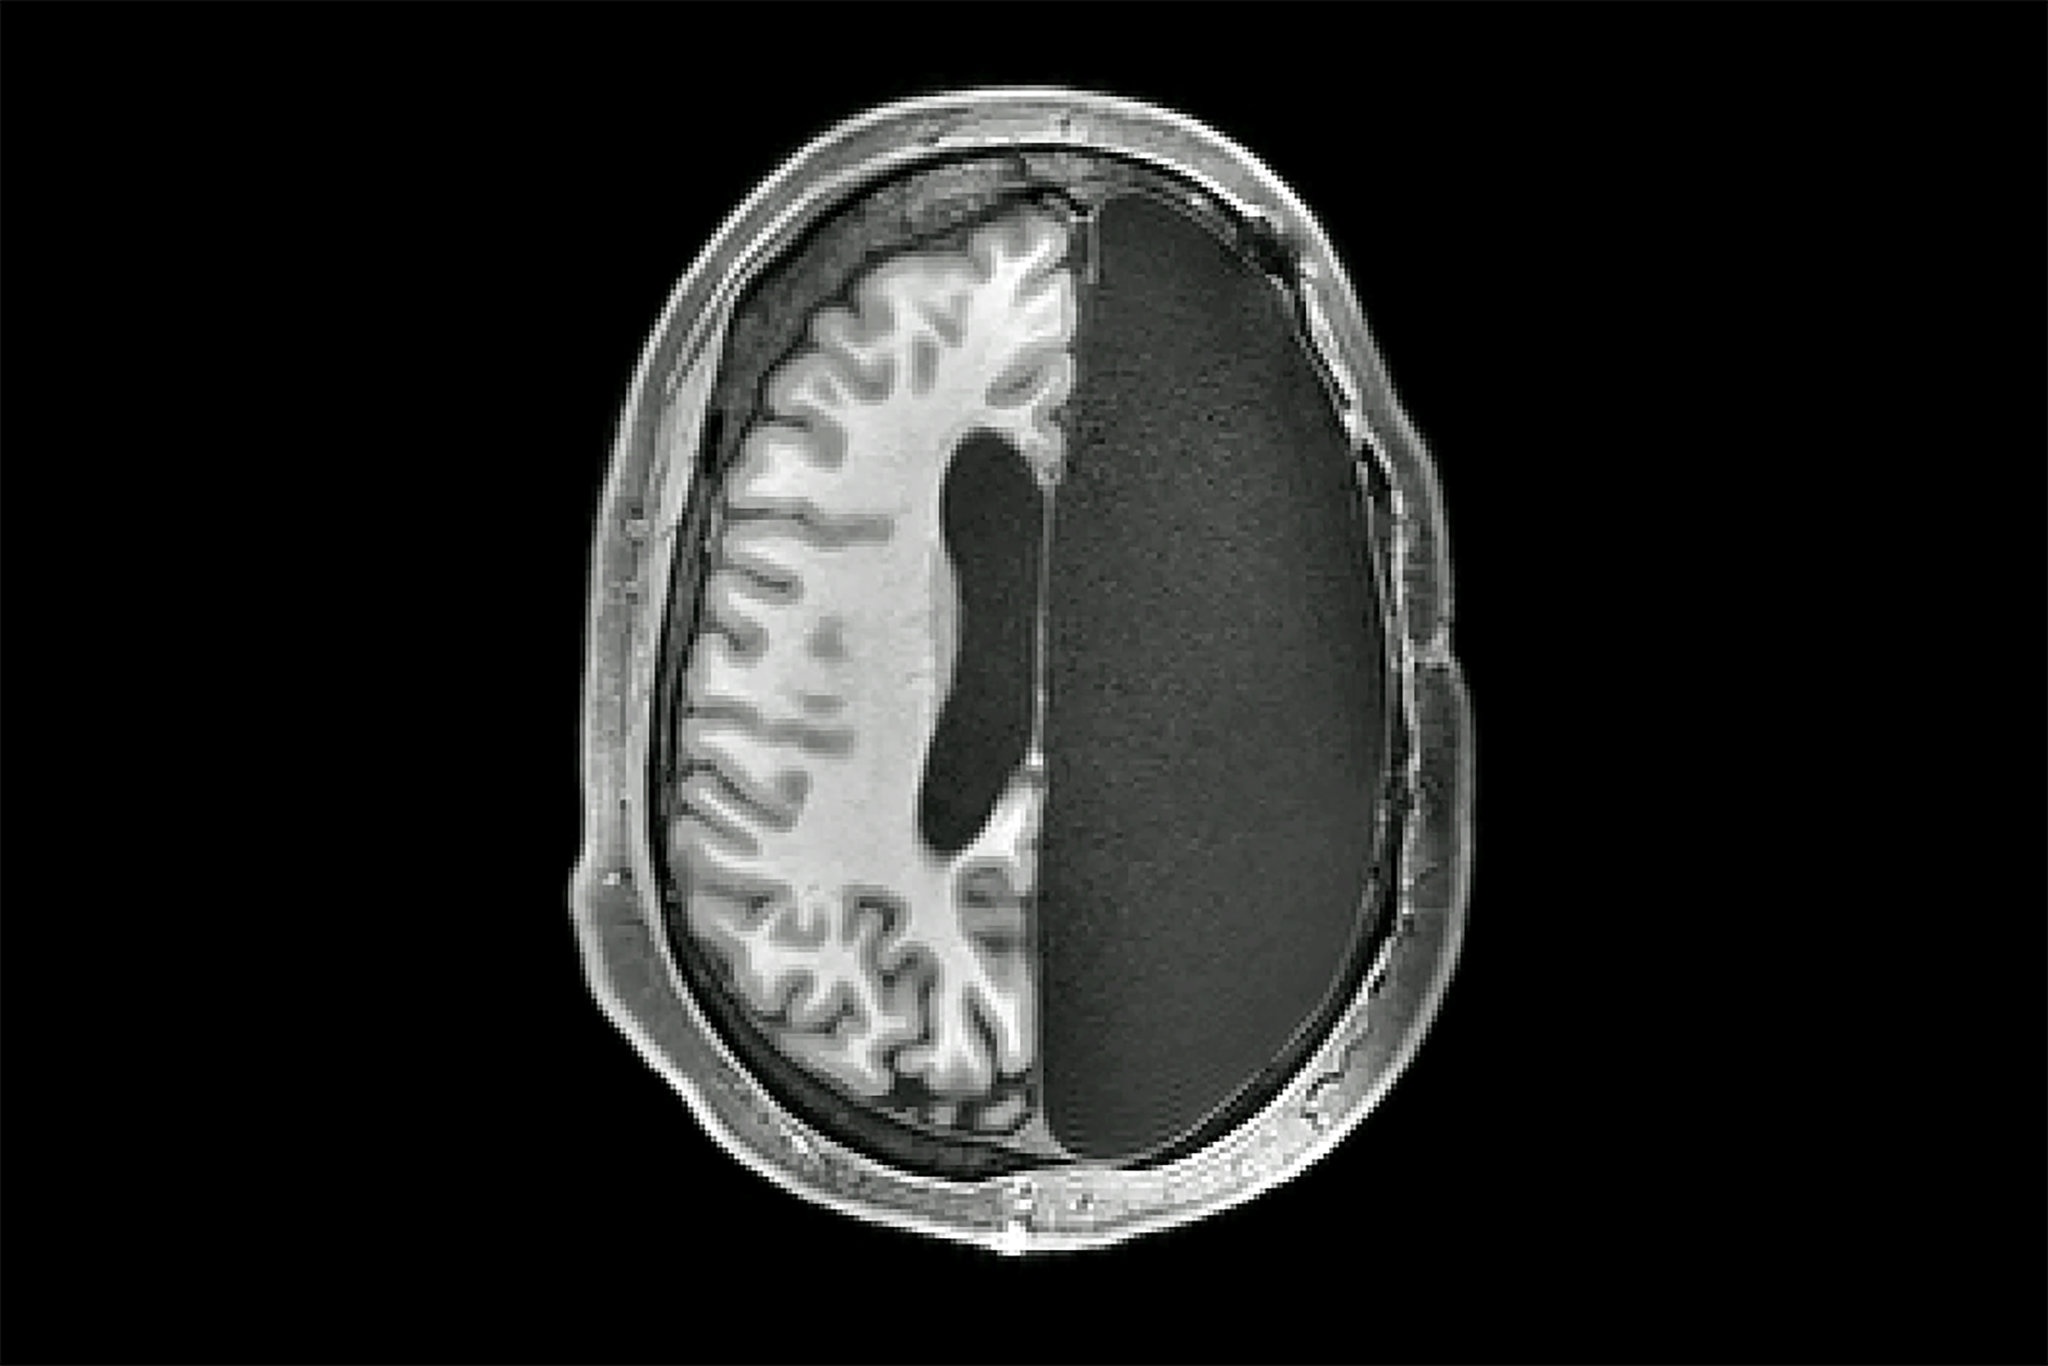

![]() |

| Não bộ có thể thích nghi và hoạt động sau phẫu thuật cắt bán cầu. Ảnh: New York Time. |

Gần đây, khoa học chứng minh phẫu thuật cắt bán cầu được thực hiện tốt nhất với bệnh nhân ở độ tuổi rất nhỏ, trước khi lên 4 hoặc 5. Trẻ em có thể lấy lại chức năng bình thường khi lớn lên.

“Mặc dù hiện tượng não dẻo phát triển mạnh hơn ở thời thơ ấu, nghiên cứu mới lại cho thấy rằng phẫu thuật không nên kéo dài quá một ngày”, tiến sĩ Gupta nói.